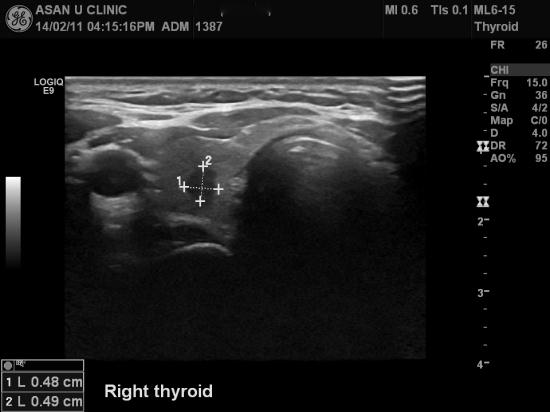

아산유외과 개원 후 18번째 갑상선암 진단.

건강검진으로 시행한 갑상선초음파상 이상소견으로 본원에

세침검사 의뢰되신 34세 여성분입니다.

세침검사 결과 갑상선에 유두암으로 진단되셨습니다.

갑상선결절의 크기 자체가 0.5cm전후로 작아서

매우 좋은 예후가 수술후 있을것으로 보입니다.